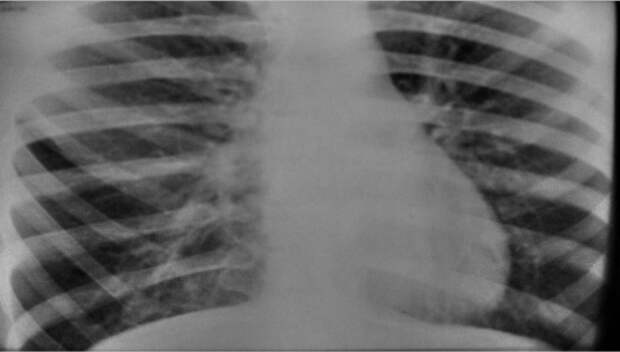

Симптомы и лечение инфильтративного туберкулеза легких

Раздел: Снимки-откровения